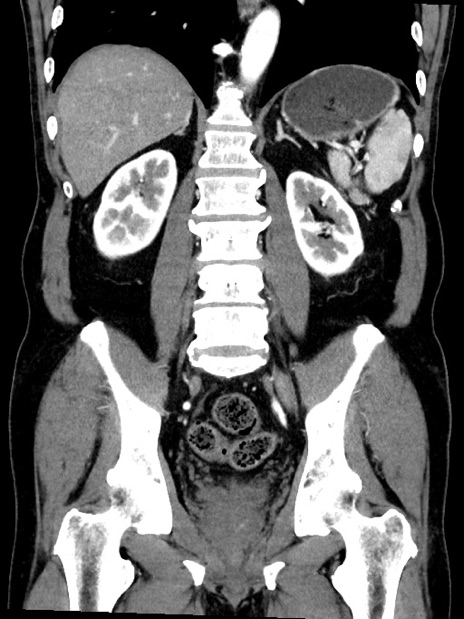

症例35(冠状断像)

【症例】70歳代 男性

【主訴】腹部膨満、嘔吐

【現病歴】昨日より腹部膨満感出現。本日増悪し、仙痛出現。嘔吐あり、受診。

【既往歴】糖尿病、胆摘後

【身体所見】BP 149/80mmHg、HR 74/min、BT 35.9℃、腹部:膨満、軟、圧痛なし。腸雑音減弱あり。上腹部正中切開瘢痕あり。

【データ】WBC 13500、CRP 1.72